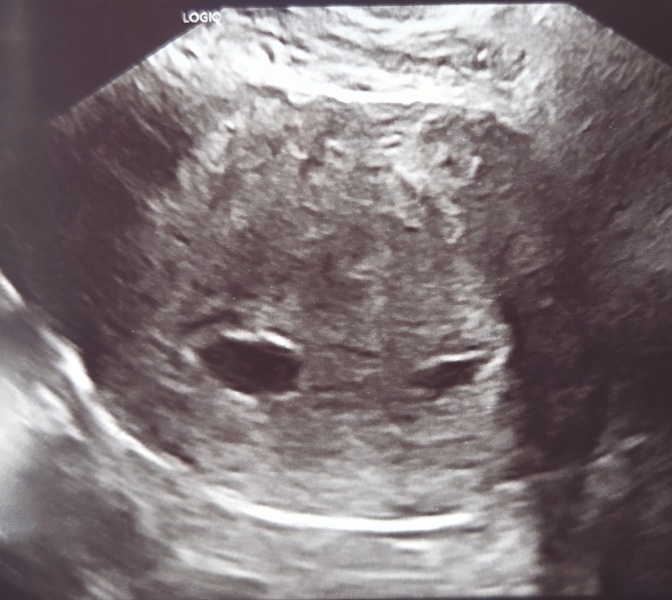

Had an ultrasound today internal one and as soon as the screen came on my husband said is that twins and the sonographer said you've got a good eye. As the scan went on something was visible in the sac on the left but not yet in the sac on the right which made him question if it was a hematoma or a second sac. My friend had twins and her scan looked very similar to mine. Whats other peoples thoughts and opinions? Had bloods done as images were not very clear to determine via pregnancy but we definitely seen a flicker in one sac

Hi, no he didnt. This was an NHS scan and I was pretty disappointed leaving the scan room. He basically said one sac had something inside but cant say for definite if its a yolk sac/fetal pole as it was so close to the edge of the sac, then said he couldnt see anything in the other sac and it may be a hematoma? ... ive had a hematoma with previous babies and its never been noticeable like that sac was. He also said when he moved the probe the smaller sac was like a sausage shape. As I said in original post as soon as the internal probe went in my husband said instantly is that twins, two sacs? ... he replied good eyes and then still didnt confirm a viable pregnancy as it wasnt a clear image. Ive had internals before and feel he wasnt using enough pressure to get a good image as normally during internals they have a good look around and it is uncomfortable at times. I had blood test done which will be repeated on monday and another scan on 5th Jan was just looking for other opinions. On the the scan report he wrote 2 sacs? So I think he was unsure too which wasn't the best